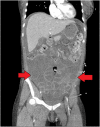

Female with peritonitis and abdominal distention